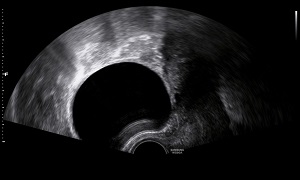

• Simple Ovarian Cyst: Clear fluid filled cyst is known as simple ovarian cyst.

• Findings: A well defined, well encapsulated fluid filled sac in ovary/ adnexal region. A clear fluid filled cyst is always benign. Presence of internal echoes is S/O blood/pus or substance with high molecular weight (which could be haemorrhagic cyst, chocolate cyst or dermoid).